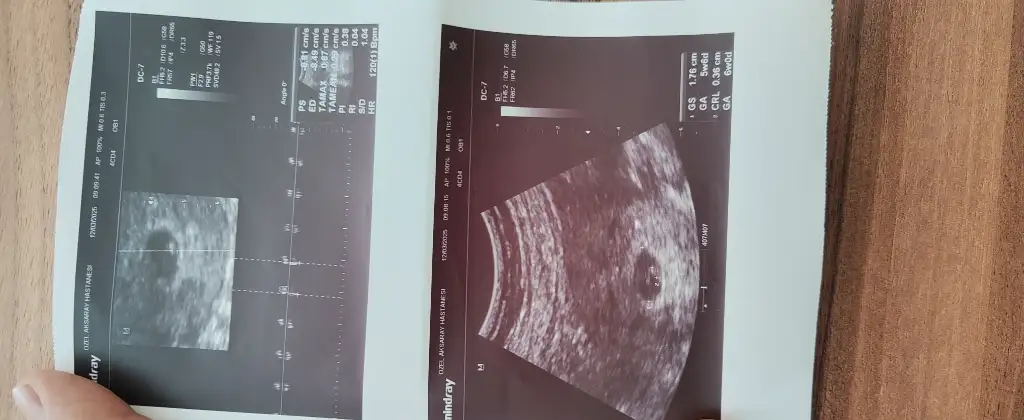

Benim icinde tahminde bulunabilir misiniz 11+4 haftalıkErkek bu bencedoktor söylemedi mi? Kaç haftalık burda

Bu kız bebek benceBenim icinde tahminde bulunabilir misiniz 11+4 haftalık

Merhaba onun nub teorisine göre çıkıntısı paralel durduğu için kız diye tahmin ettim,sizin görüntü karından alındıysa ramzi teorisine göre erkek duruyor6 haftalik tahminde bulu